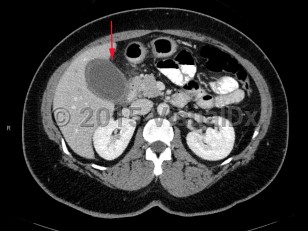

Acute cholecystitis is a surgical emergency of the biliary tract that can be life-threatening if appropriate treatment is not initiated promptly. Acute cholecystitis is characterized by gallbladder wall inflammation. Patients classically present with right upper quadrant (RUQ) abdominal pain, fever, and leukocytosis. Acute cholecystitis is further categorized by the presence of gallstones as calculous or acalculous.

Acute calculous cholecystitis occurs when a gallstone blocks the cystic duct, impairing gallbladder drainage. Temporary obstruction can cause biliary colic. Sustained obstruction can result in gallbladder dilation, wall inflammation, subsequent wall thickening, and pericholecystic fluid accumulation.